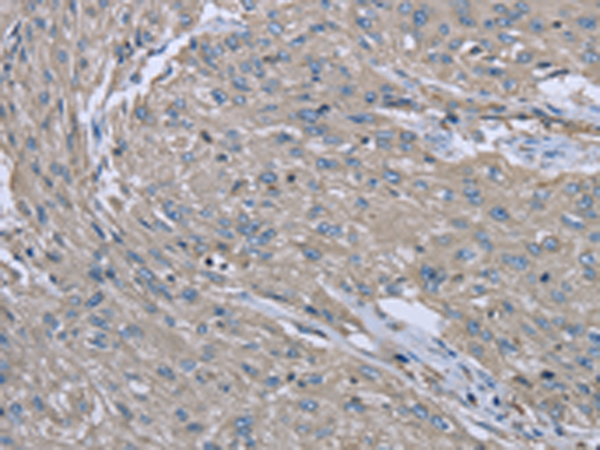

分类: 科研抗体货号: P08301别名: AMDD应用: IHC反应种属: Human